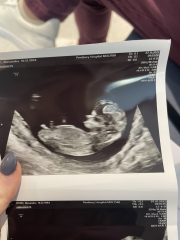

xalexandra · 07/10/2022 10:25

Just had my 12 week scan and all fine and healthy 🥰🥰 I mentioned about the fluid again after yesterdays hospital trip and she said it seems fine 🥰

@xalexandra yaaaay! So happy for you ! Gorgeous scan, looks like a boy to me 🤣 x

@Sprinklerainbows omg someone else said boy! Maybe you're on to something!!

@xalexandra It’s the nub looks high up but I’m no expert by any means 🤣 I have a boy and it’s the best!